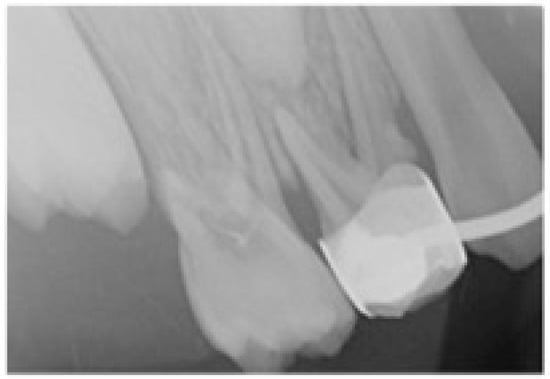

2.2. Treatment Protocol